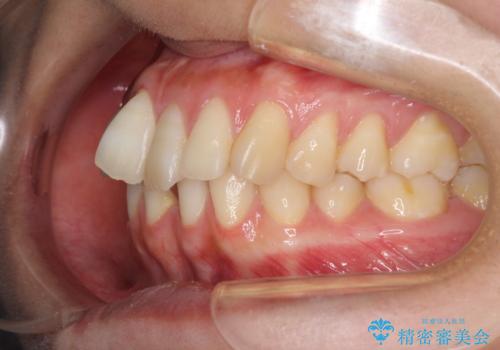

下顎前歯が2歯欠損しており、スペースになっており、上顎は叢生歯列となってしました。

奥歯の咬み合わせを考えると、理想的には2歯、最低でも1歯は下顎前歯の欠損部にインプラントやブリッジにより歯数を増やす必要がありました。

周囲の歯を削らないようにするためインプラントがおすすめとなりますが、歯根の移動が不十分な場合にはインプラントを埋入する幅が獲得できないため、その場合にはオールセラミックブリッジにより補綴治療を行うこととして、矯正治療を行うこととしました。

当初は上記計画でしたが、レントゲン撮影よりインプラント埋入は困難と判断され、患者様と相談の上、歯を削ってブリッジとするよりも、奥歯の咬み合わせを多少妥協することとなっても、スペースを閉じて仕上げていくこととしました。